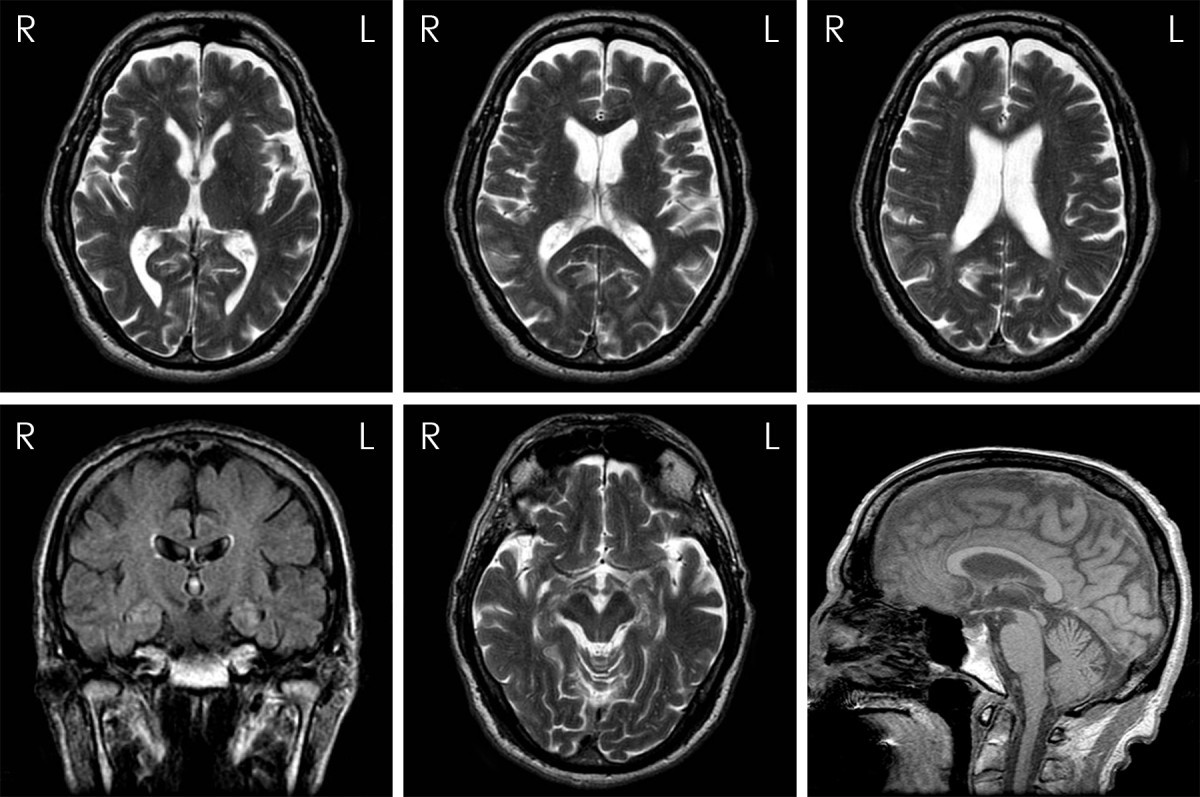

Figure 1 from Extending the range of differential diagnosis of chronic traumatic encephalopathy Boxer's Encephalopathy Definition This review seeks to establish an evidence base for informed decision making in this regard. Changes in brain volume and cognitive skills may predict the onset of chronic traumatic encephalopathy, or cte. Chronic traumatic encephalopathy (cte) is a degenerative brain disorder that happens due to repeated head impacts. Chronic traumatic encephalopathy (cte) is defined as a distinctive neurodegenerative disease that. Boxer's Encephalopathy Definition.

Figure 2 from Extending the range of differential diagnosis of chronic traumatic encephalopathy Boxer's Encephalopathy Definition Chronic traumatic encephalopathy (cte) is a degenerative brain disorder that happens due to repeated head impacts. Chronic traumatic encephalopathy (cte) is a progressive degenerative disease of the brain known to occur in individuals who have. Chronic traumatic encephalopathy (cte) is a form of brain degeneration caused by repeated trauma to the head. This review seeks to establish an evidence base. Boxer's Encephalopathy Definition.